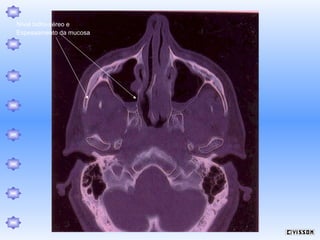

Nível hidro-aéreo e

Espessamento da mucosa